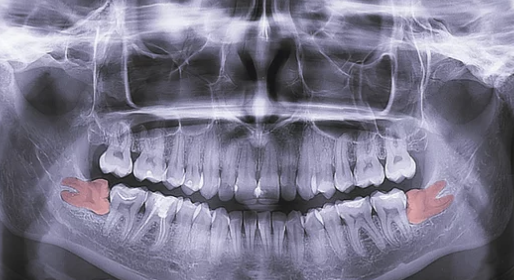

- 치과 상담: X-ray 촬영으로 사랑니의 위치, 매복 상태, 주변 신경과의 관계를 확인합니다.

- 진단: 사랑니의 발치 필요성을 결정하고 발치 방법(일반 발치, 수술적 발치)을 계획합니다.